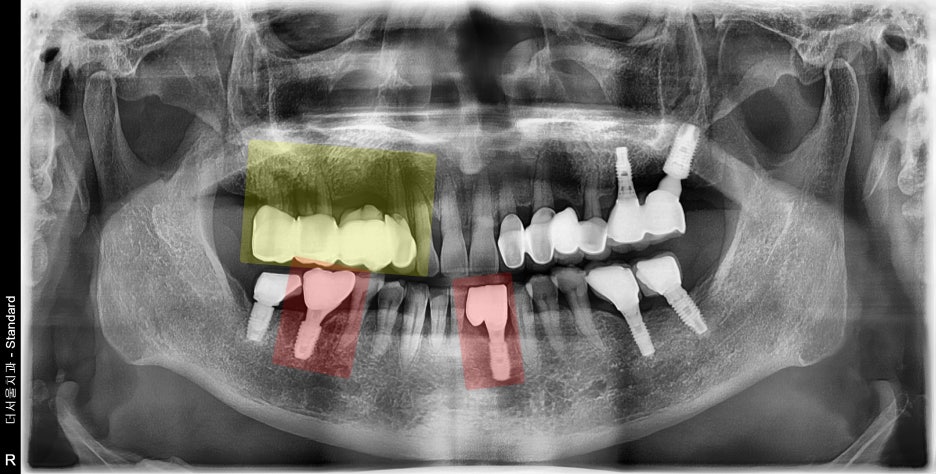

빨간색으로 칠해진 곳은, 저번에

치료를 끝마쳤던 곳이고

이번에는 노란색으로 칠해진 곳에

어금니 임플란트를 심어드릴 예정입니다.

이미 보철 수복이 다 되어있으나,

여기 또한 치조골 소실 및 염증 발생에

따라서 구강 위생 관리가 잘 되지 않은 곳이네요.

치아가 흔들리는 증세는 없었으나,

통증이 심했던 상황이였고

뼈도 많이 녹아있었기에 발치 후

임플란트 결정을 내리게 되었습니다.